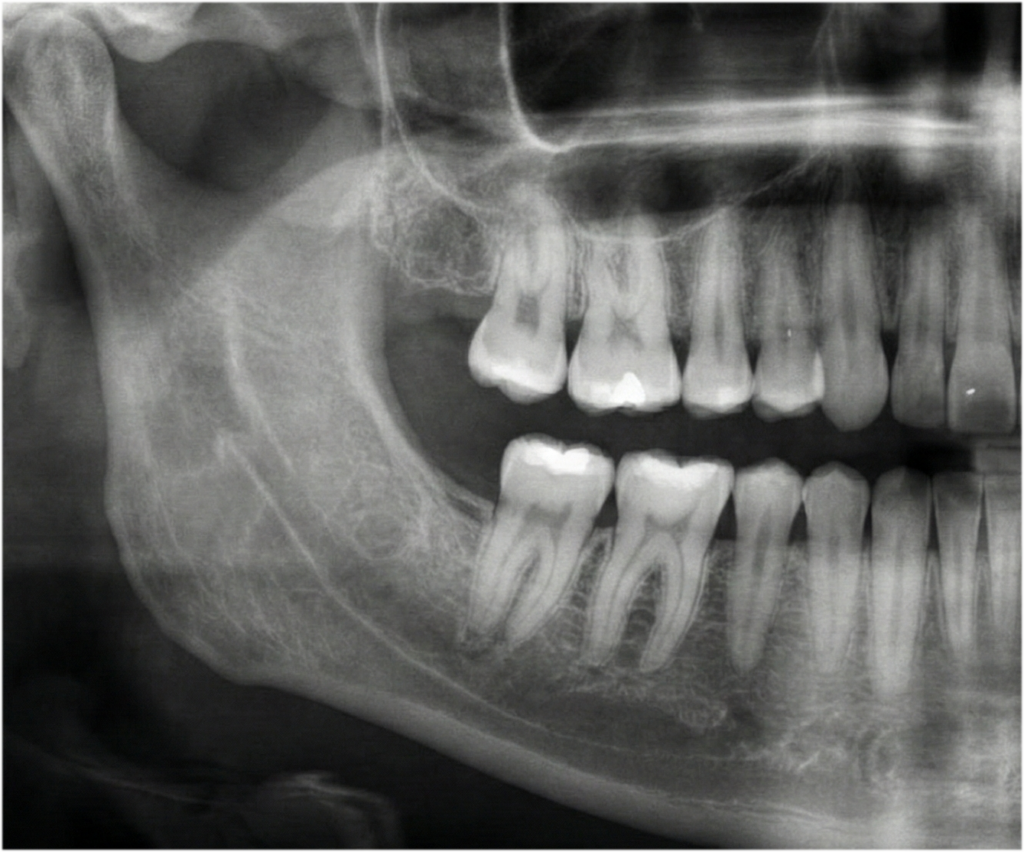

단순 발치부터 대학병원 전원이 필요한 완전 매복 사랑니까지. 풍부한 임상 데이터를 보유한 원장이 직접 진단하고 시술합니다. 어려운 사랑니일수록 경험이 중요합니다.

정밀 진단과 안전 최우선

최첨단 CT를 통해 사랑니의 뿌리 형태, 하치조 신경과의 거리를 0.1mm 단위까지 정밀 분석합니다. 정확한 진단이 안전한 시술의 첫걸음입니다.